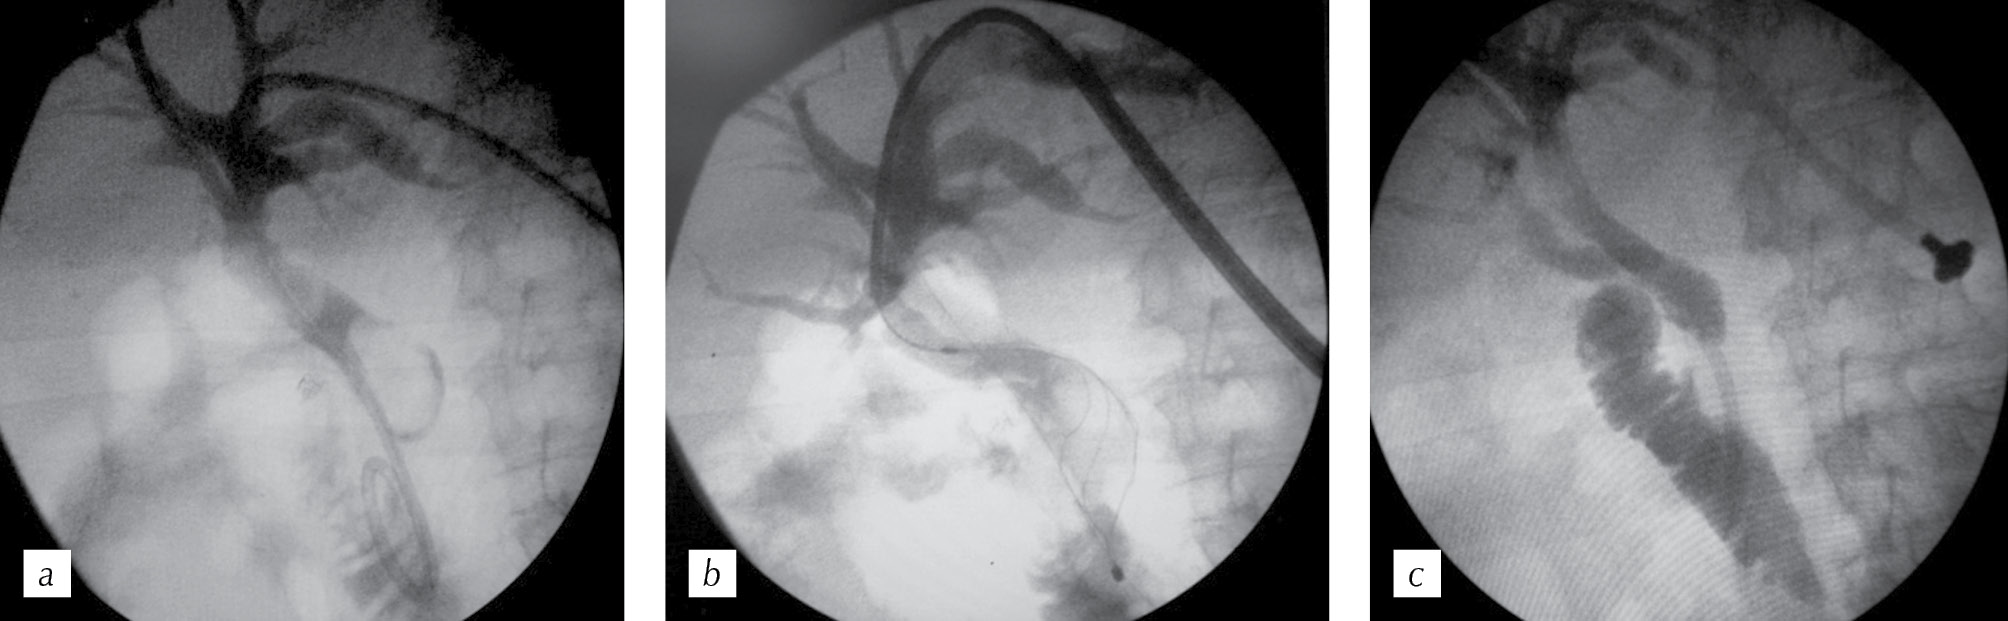

Patient B., 52 years old, was hospitalized in the clinic with symptoms of obstructive jaundice. The patient had a history of combined treatment for cancer in the upper ampullar segment of the rectum in the area of the anterior rectum resection, an extended right-sided hemihepatectomy, and five courses of palliative chemotherapy. Initially, a stricture at the hepatic hilar level was regarded as a progression of the oncological process (Fig. 4). At the first stage, external cholangio-drainage was performed, and at the second stage, stenting (an uncoated SNS was used) was performed. After one year, the patient was re-hospitalized due to the relapse of jaundice.

Fig. 4. Stages of surgical treatment of the patient with benign stricture of the common hepatic duct: a — direct cholangiography (the arrow indicates the stricture zone); b — stage of stenting (the arrow indicates the stent); c — cholangiogram (the arrow shows the area of stent obstruction); d — suprapapillary endoprosthesis placement (the arrow shows the endoprosthesis installed through the stent lumen)

Рис. 4. Этапы хирургического лечения пациентки с доброкачественной стриктурой общего печеночного протока: a — прямая холангиография (стрелкой указана зона стриктуры); b — этап стентирования (стрелка указывает на стент); c — холангиограмма (стрелкой показана зона обтурации стента); d — супрапапиллярное эндопротезирование (стрелкой отмечен эндопротез, установленный через просвет стента)

At the time of hospitalization, the patient had stabilization of the oncological process. Direct cholangiography revealed obturation of the upper jaw of the stent. A percutaneous intraluminal biopsy and recanalization of the stricture zone were performed. The pathological examination revealed fragments of granulation tissue, that is, the presence of benign strictures along the left lobar duct. Then, suprapapillary endoprosthesis replacement was performed due to the joint return of the MPD and the CBD. The patient’s case has been followed up for two years. During this time, the endoprosthesis has been replaced twice, and the patient is currently undergoing targeted therapy for disease progression in the form of metastases to the lungs and the liver.